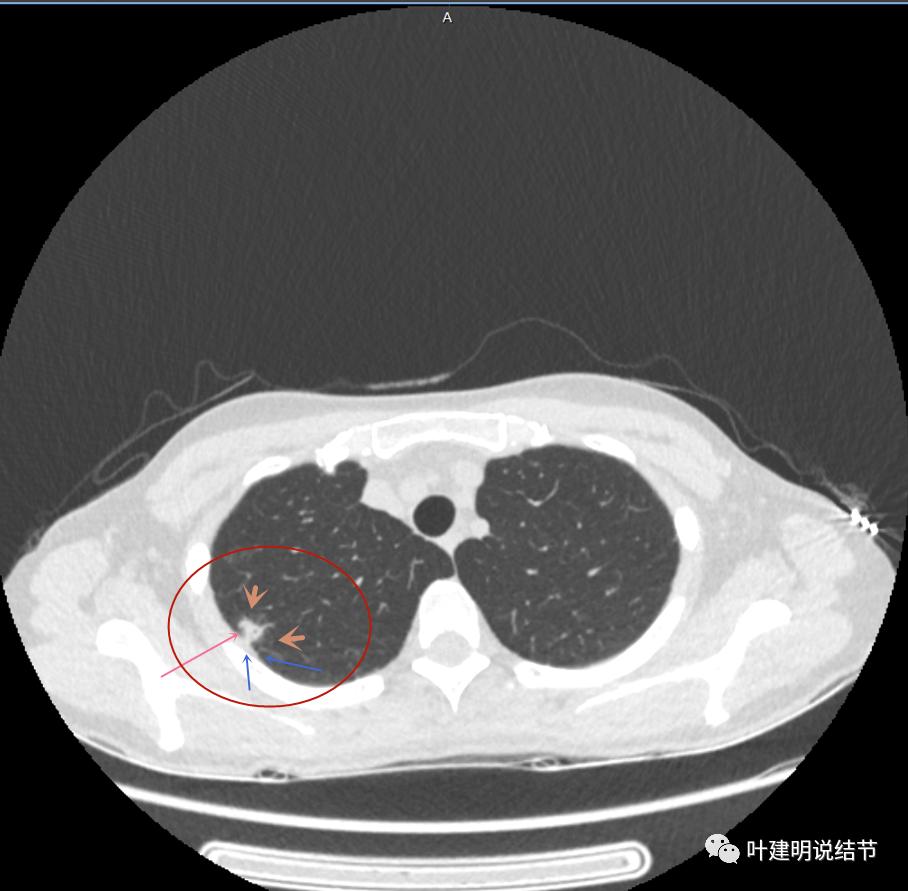

主病灶出现,粉色箭头示病灶密度较高,边上有磨玻璃影,甚淡(砖色箭头)

病灶有空洞(黄色箭头),主病灶边上见条索状高密度影(细红色箭头),邻近胸膜有粘连(蓝色箭头)

邻近胸膜明显增厚,且广基底,主病灶前方有小片磨玻璃影

主病灶与胸膜间基本相连,模糊清(蓝色箭头),主病灶壁厚薄欠均,边上有高密度条索状(桔色箭头)